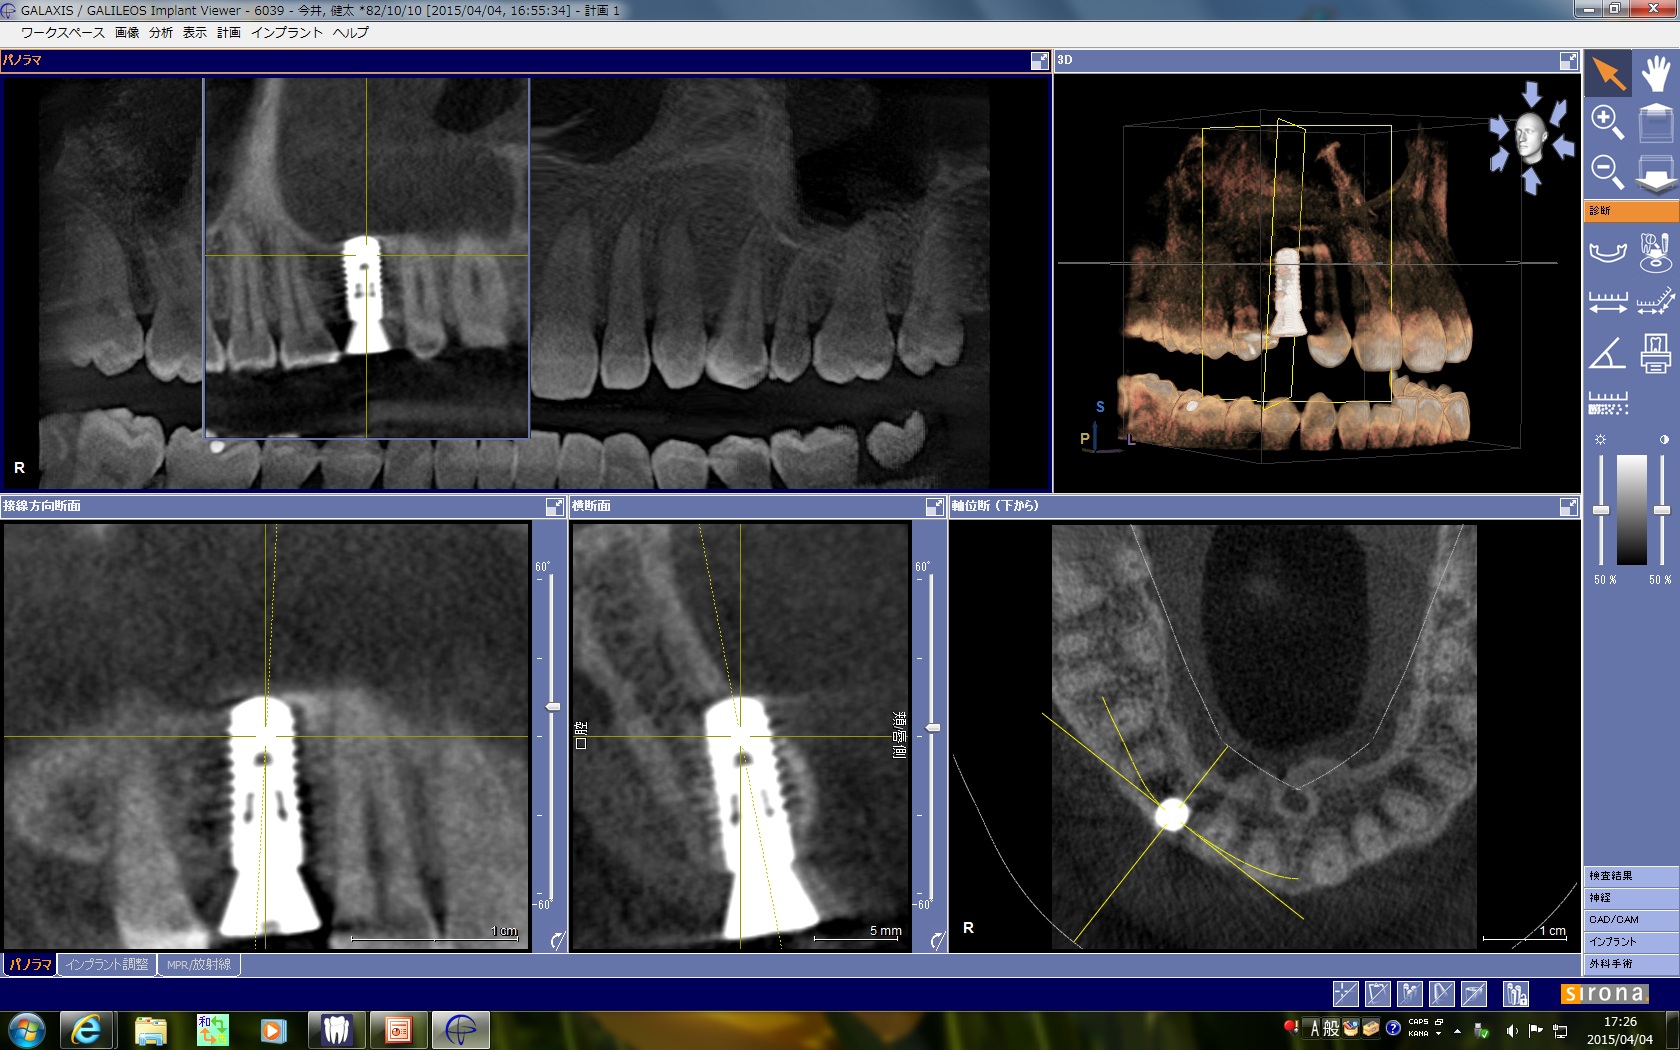

術前のプランニングソフトでインプラントの埋入の位置、角度、深さを3次元的に計画します。

術後のCTですが、唇側の皮質骨でバイコルチカルの固定が期待できます。